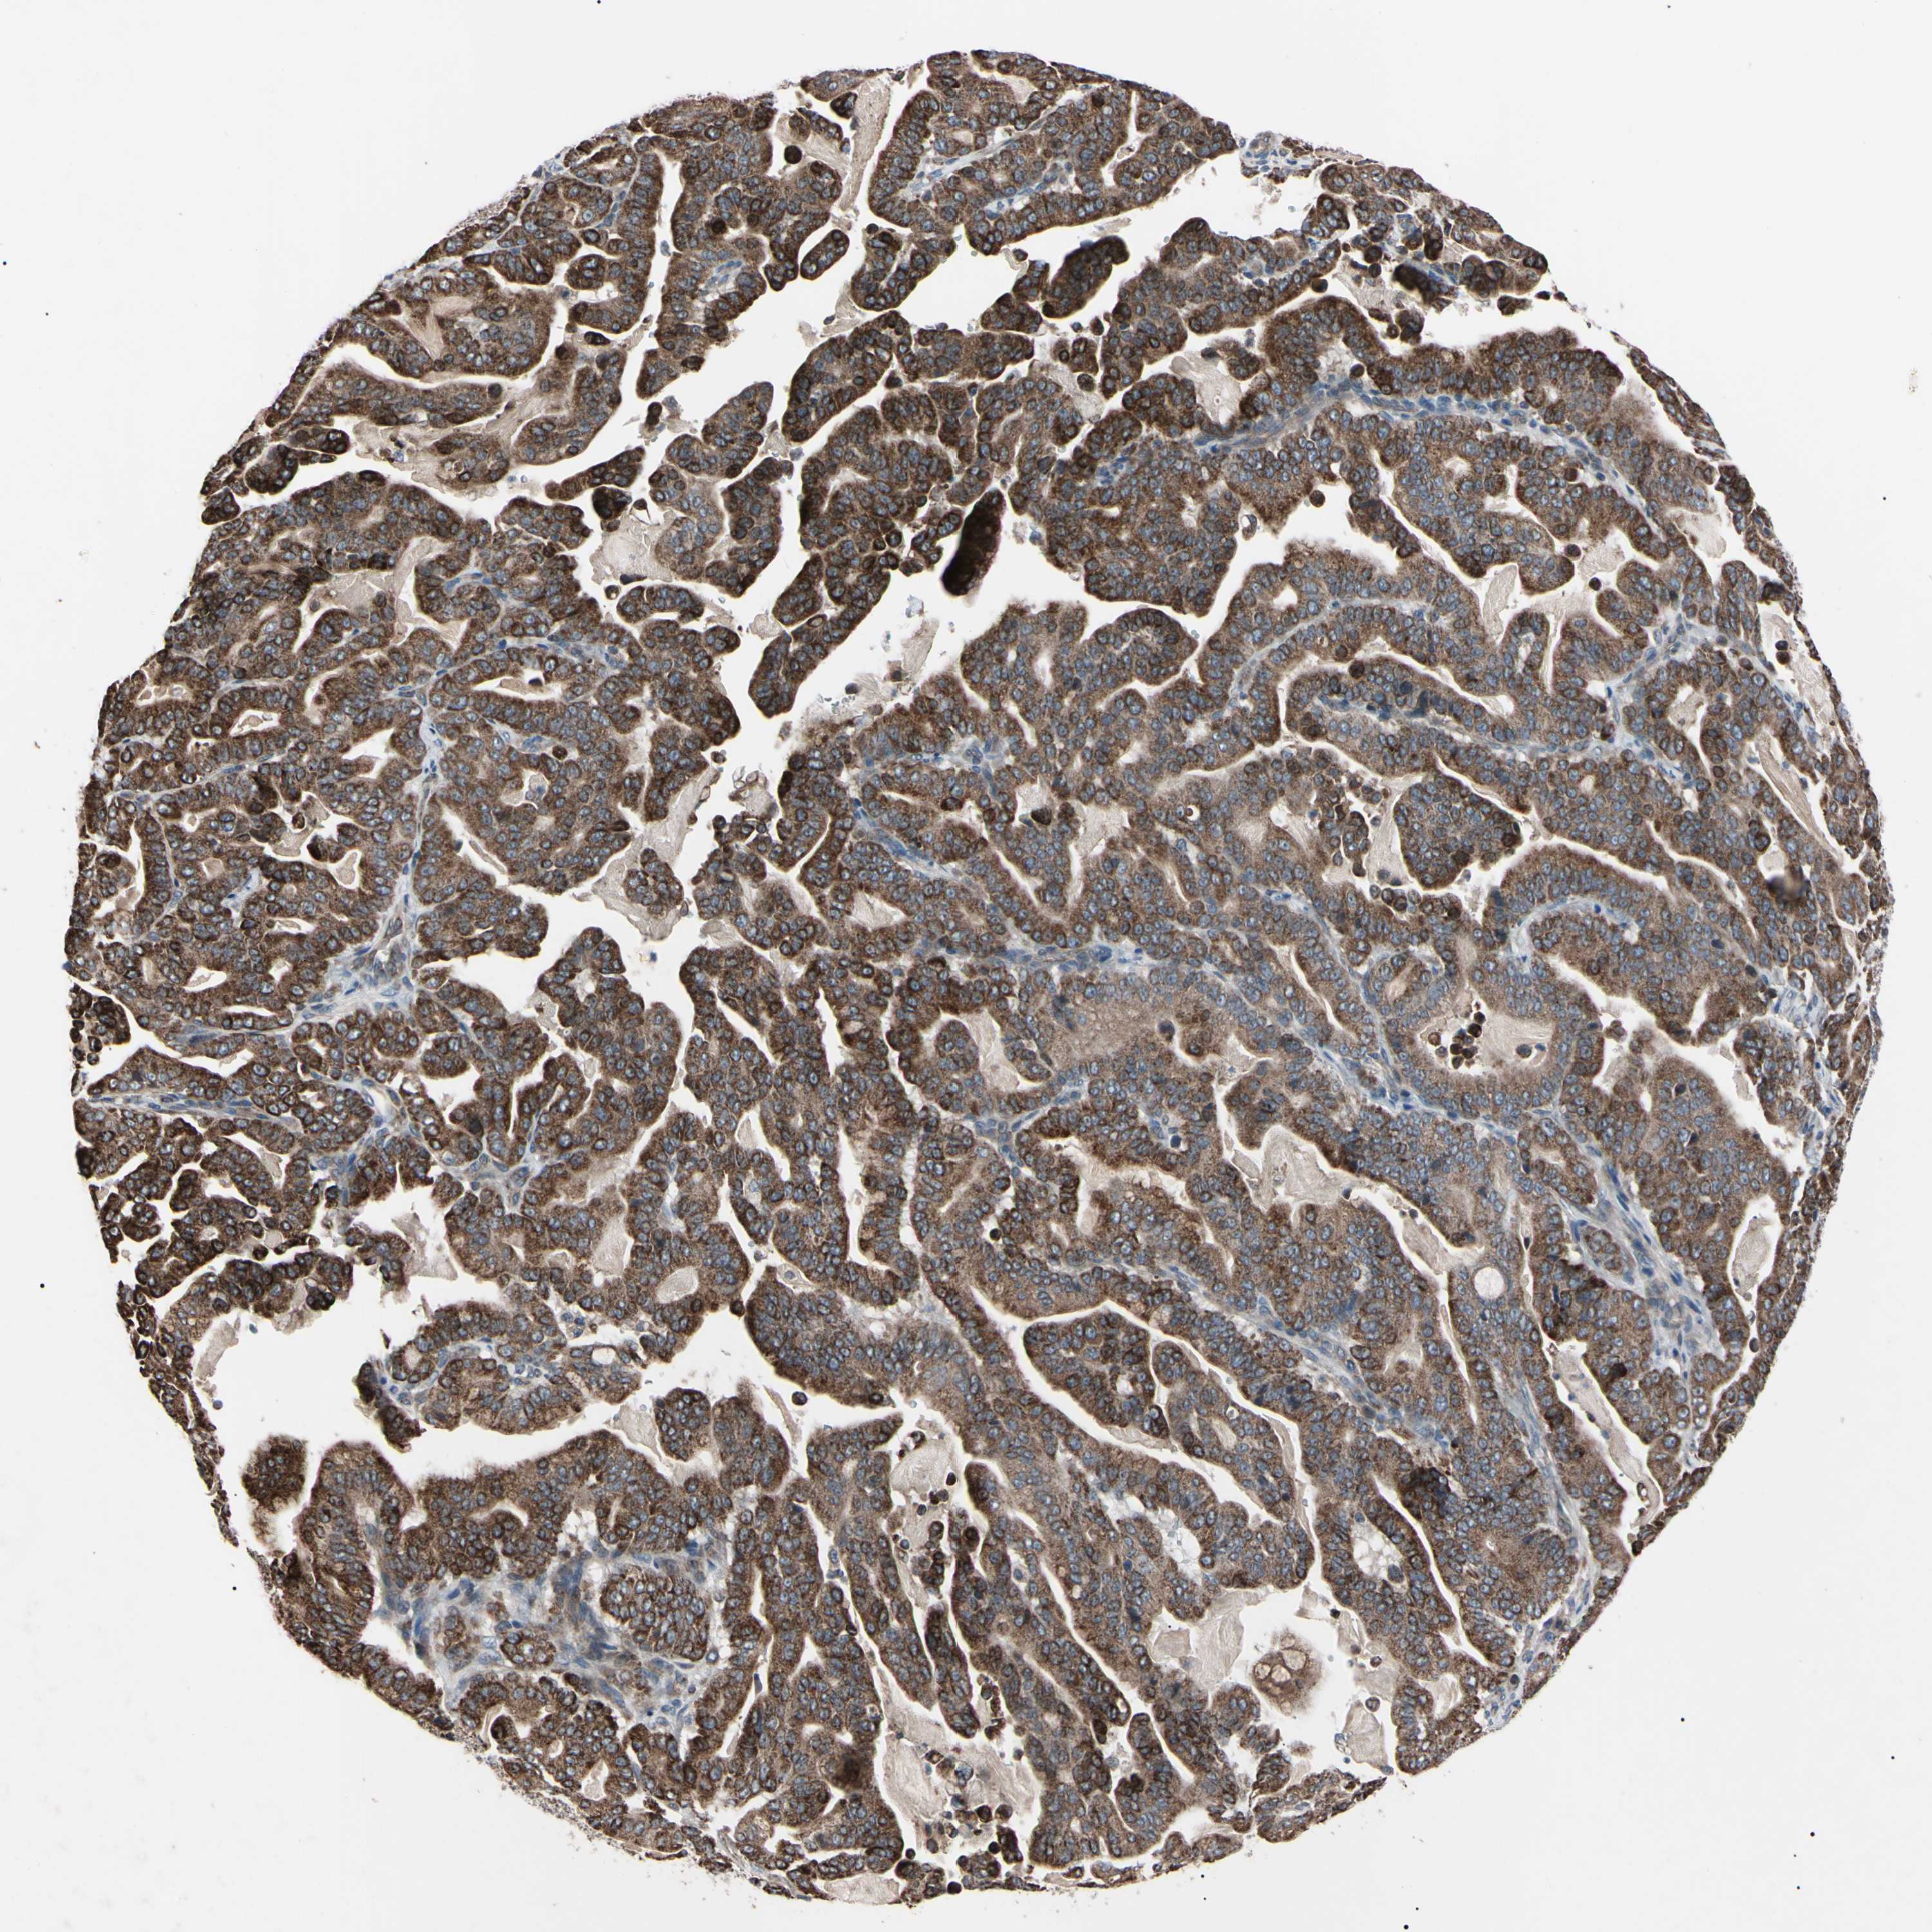

PANCREATIC CANCER - Protein expressioni

A mouse-over function shows sample information and annotation data. Click on an image to view it in a full screen mode. Samples can be filtered based on level of antibody staining by selecting one or several of the following categories: high, medium, low and not detected. The assay and annotation is described here.

Note that samples used for immunohistochemistry by the Human Protein Atlas do not correspond to samples in the TCGA dataset.

Antibody stainingi

Antibody staining in the annotated cell types in the current human tissue is reported as not detected, low, medium, or high, based on conventional immunohistochemistry profiling in selected tissues. This score is based on the combination of the staining intensity and fraction of stained cells.

Each image is clickable and will lead to virtual microscopy that enables deeper exploration of all samples and also displays staining intensity scores, fraction scores and subcellular localization as well as patient and tissue information for each sample.

Antibody HPA004102

Antibody CAB010309

Staining

High

Medium

Low

Not detected

Intensity

Strong

Moderate

Weak

Negative

Quantity

>75%

75%-25%

<25%

None

Location

Nuclear

Cytoplasmic/membranous

Cytoplasmic/membranous,nuclear

Adenocarcinoma, NOS

Adenocarcinoma, metastatic, NOS